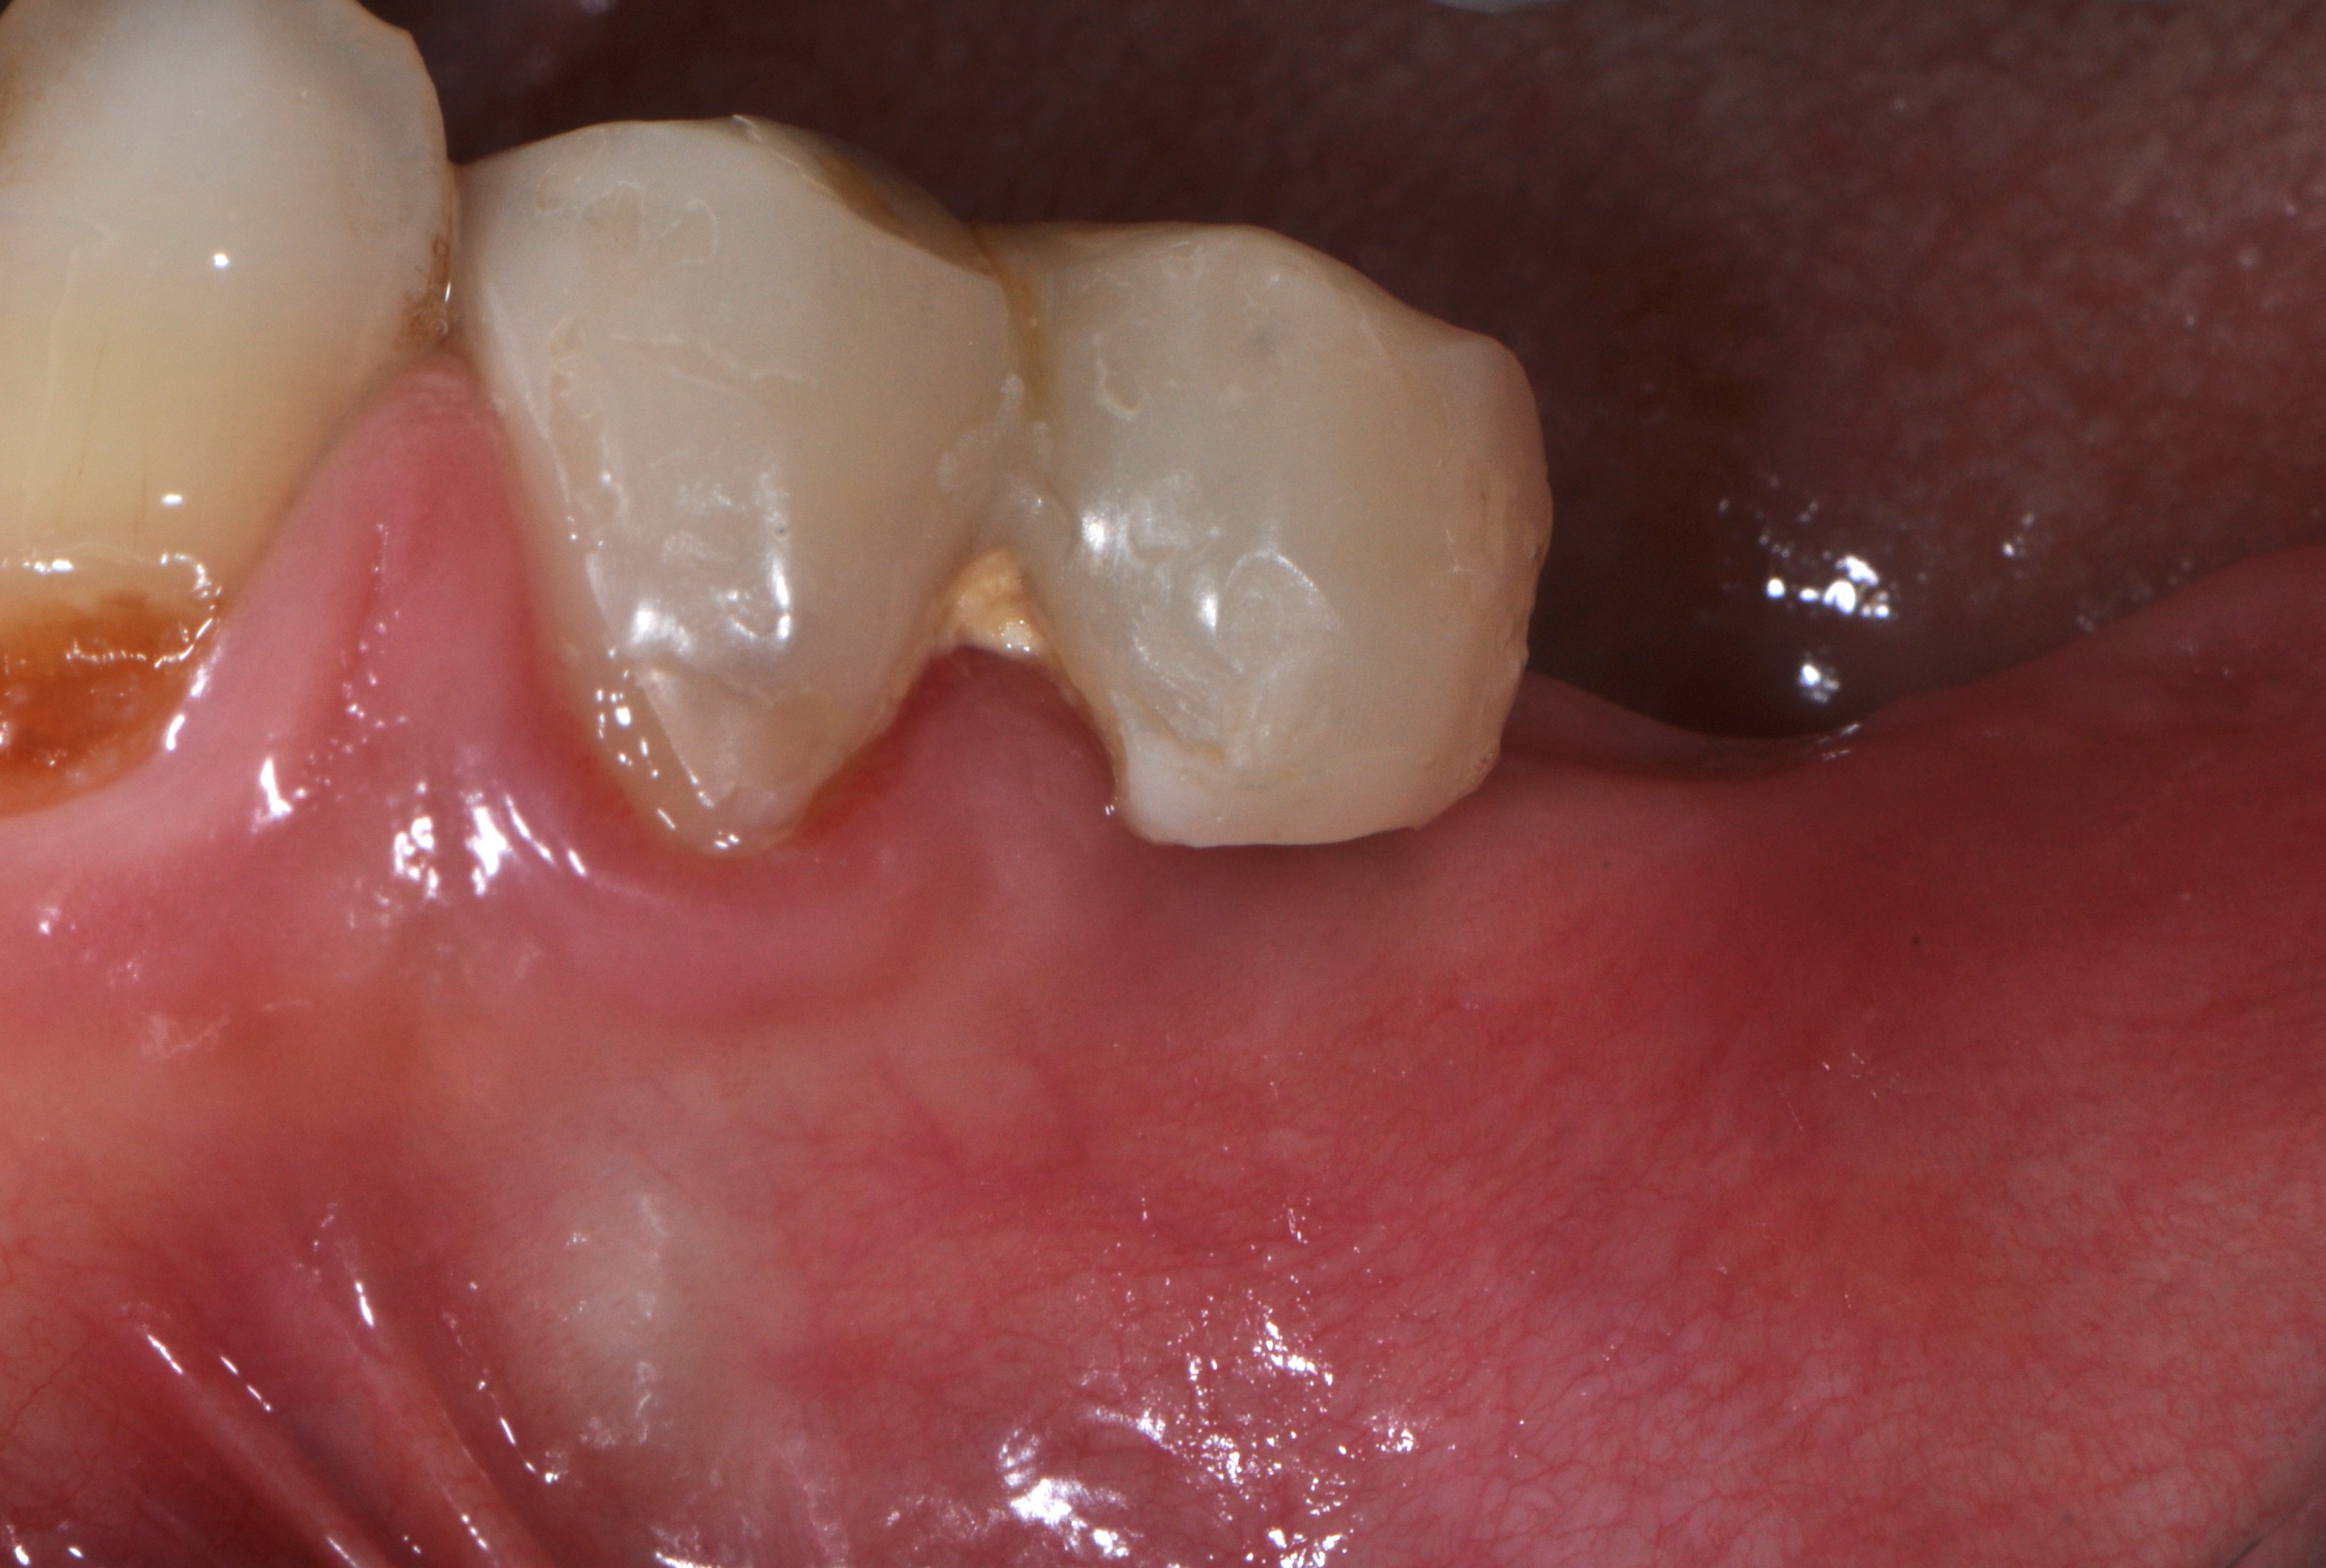

A 52-year-old patient is a referral and has been wearing an immediate provisional partial denture after replacement of her worn and fractured fixed partial denture. As a definitive treatment solution, the patient desired "beautiful and long-lasting" implant-supported single crowns. Clinically the CT-scan revealed a very narrow bone crest ("knife-edge") in the 3rd quadrant. Implant placement has been planned with a simultaneous GBR procedure.